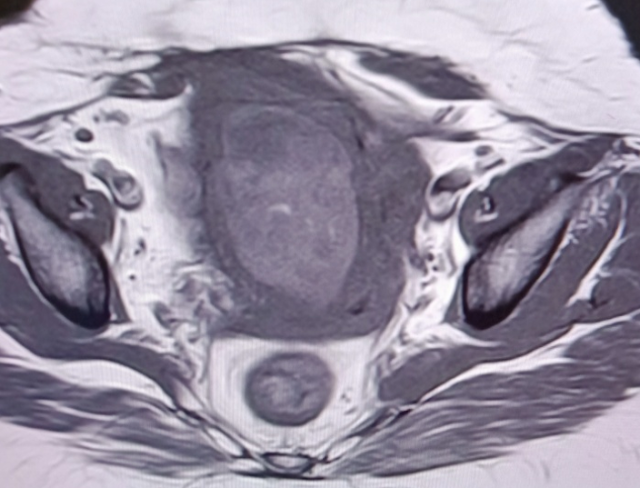

Cesarean Scar Ectopic Pregnancy- MRI - Sumer's Radiology Blog

Cesarean scar ectopic pregnancy- MRI - Sumer's Radiology Blog www.indianradiology.com

scar ectopic mri cesarean gestation assess lscs uterine previous

Cesarean scar ectopic pregnancy- MRI - Sumer's Radiology Blog sumerdoc.blogspot.com

scar ectopic cesarean mri uterine

scar ectopic pregnancy mri cesarean uterine radiology gestation assess sac lscs

scar ectopic mri cesarean uterine pelvis radiology assess gestation lscs

Cesarean scar ectopic pregnancy- mri. Cesarean scar ectopic pregnancy. Scar ectopic mri cesarean gestation assess lscs uterine previous